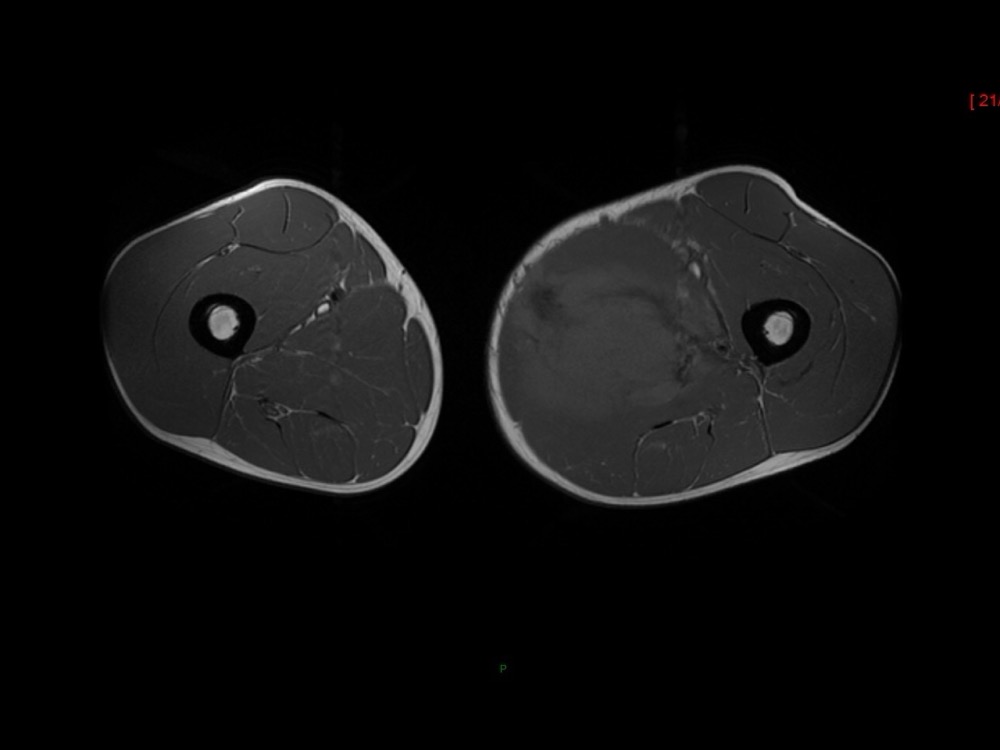

Moalla / Mihoubi-Bouvier / Drapé 18/05/2022